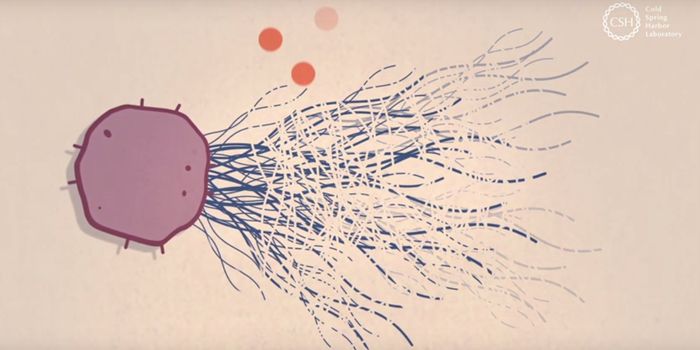

DEC 19, 2015ImmunologyDendritic cells use phagocytosis to break up molecules from pathogens to present on their cell surface to warn other lym ...